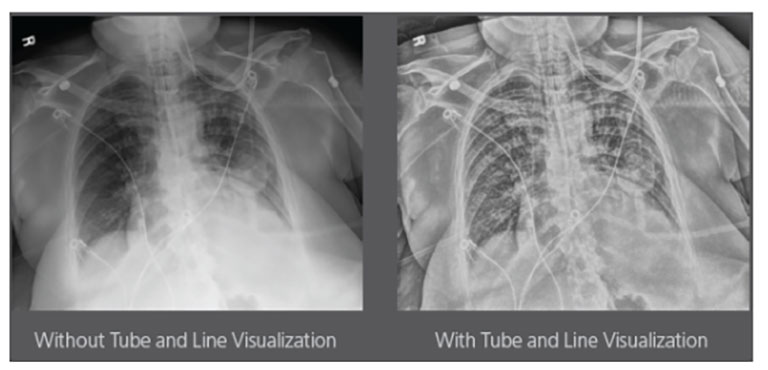

CARESTREAM Image Suite V4 MR11 has set a new standard for workflow efficiency, offering a robust set of features and functionalities to enhance clinical confidence in healthcare professionals. Using an auto-generated companion image from a single exposure, leverage a range of image processing options to increase diagnostic accuracy and enhance patient care.